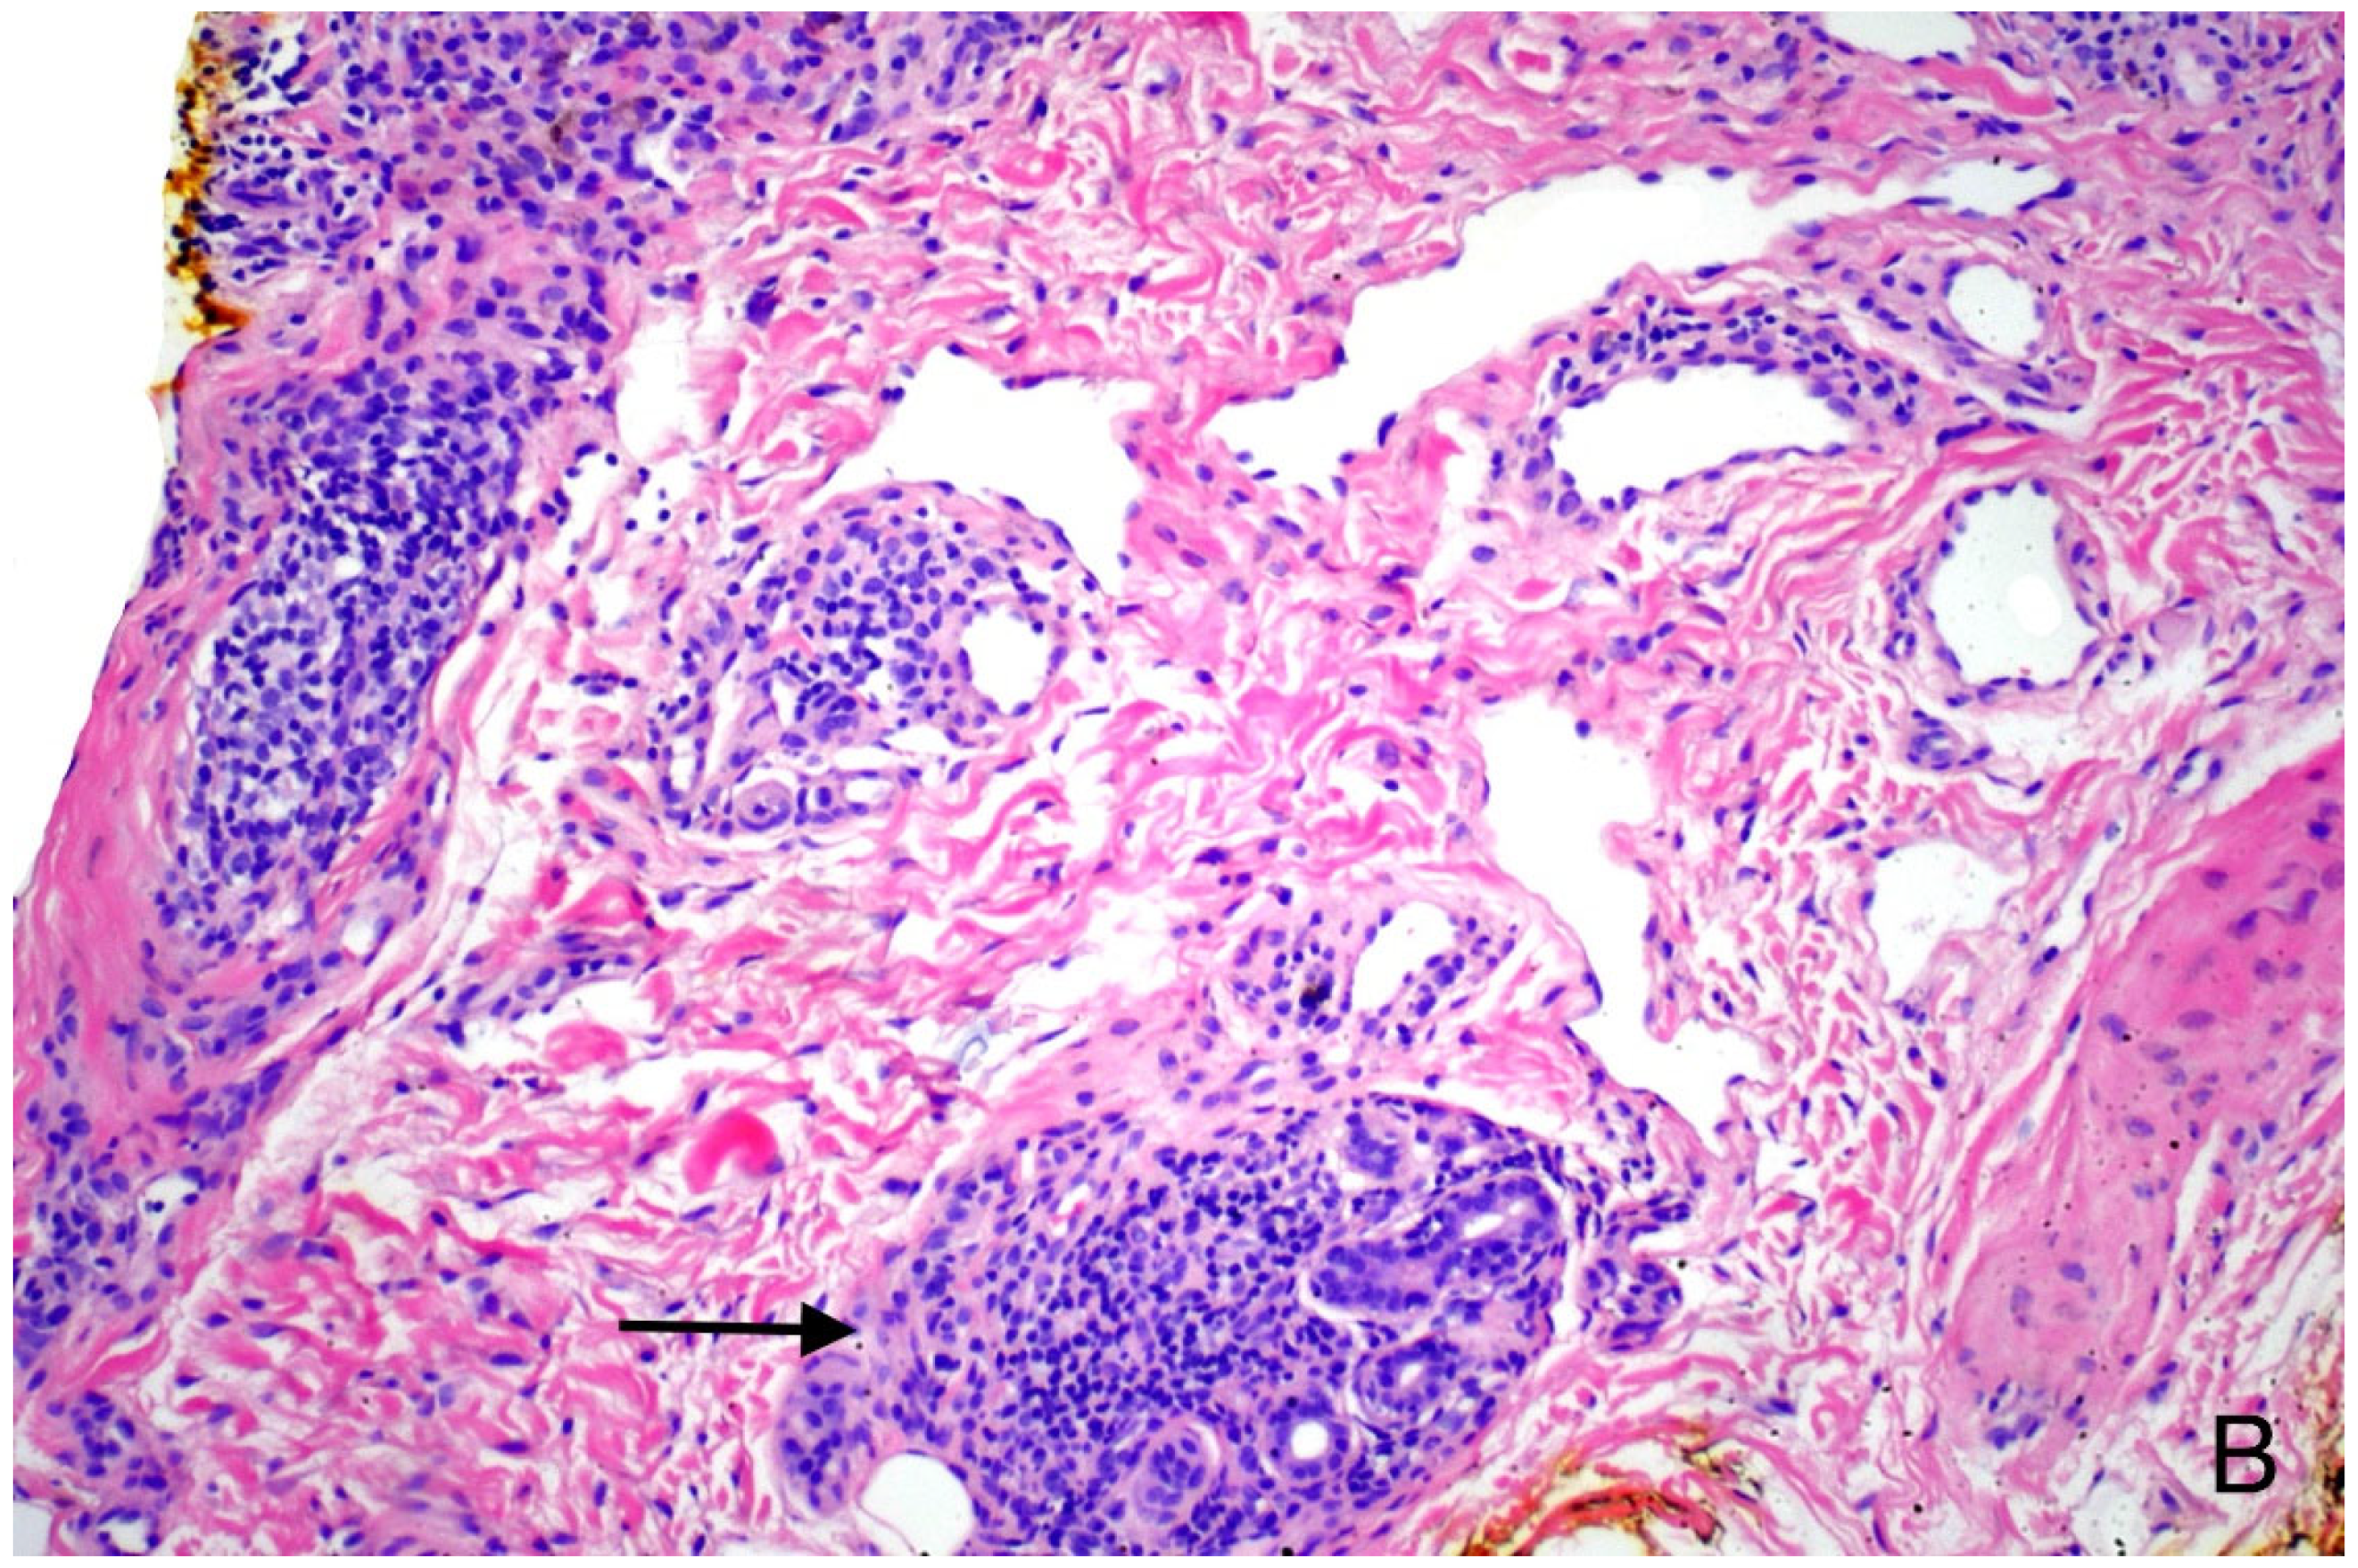

| Histopathologic | |||

| Deep Perivascular Infiltrate | Rarely seen | May be present | Often present in lichen striatus Occasionally seen in other lichenoid reactions |

| Perieccrine or Periadnexal Infiltrate | Not characteristic. May be seen in adnexotrophic variants. | Uncommon | Often seen in vaccine-induced LS. |

| Granuloma Formation | Not characteristic | May rarely be present | Seen in 1/15 cases in series reported herein. |